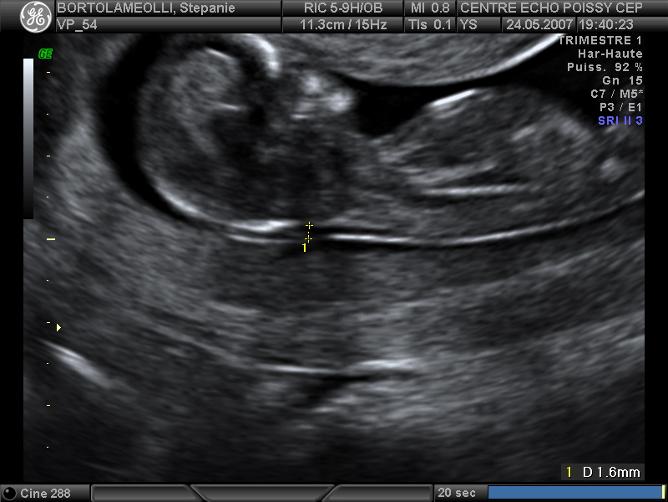

Echographies